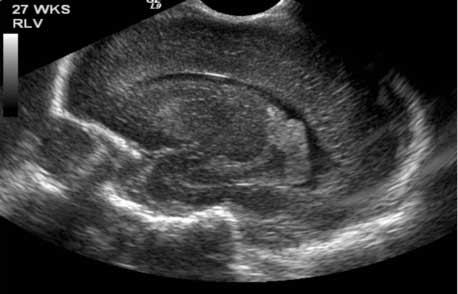

Vista lateral: ultrasonido del cerebro en recién nacido. Frente a la izquierda y parte atrás del cráneo a la derecha.

Nota: Las imágenes se muestra para fines ilustrativos. No trate de sacar conclusiones comparando esta imagen con otras en el sitio. Solamente los radiólogos calificados deben interpretar las imágenes.